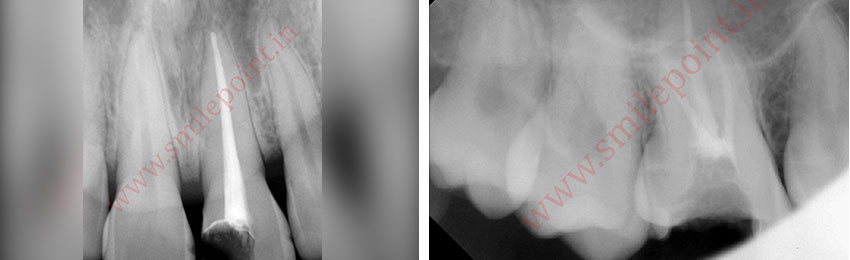

Computer assisted and navigated root canal treatment